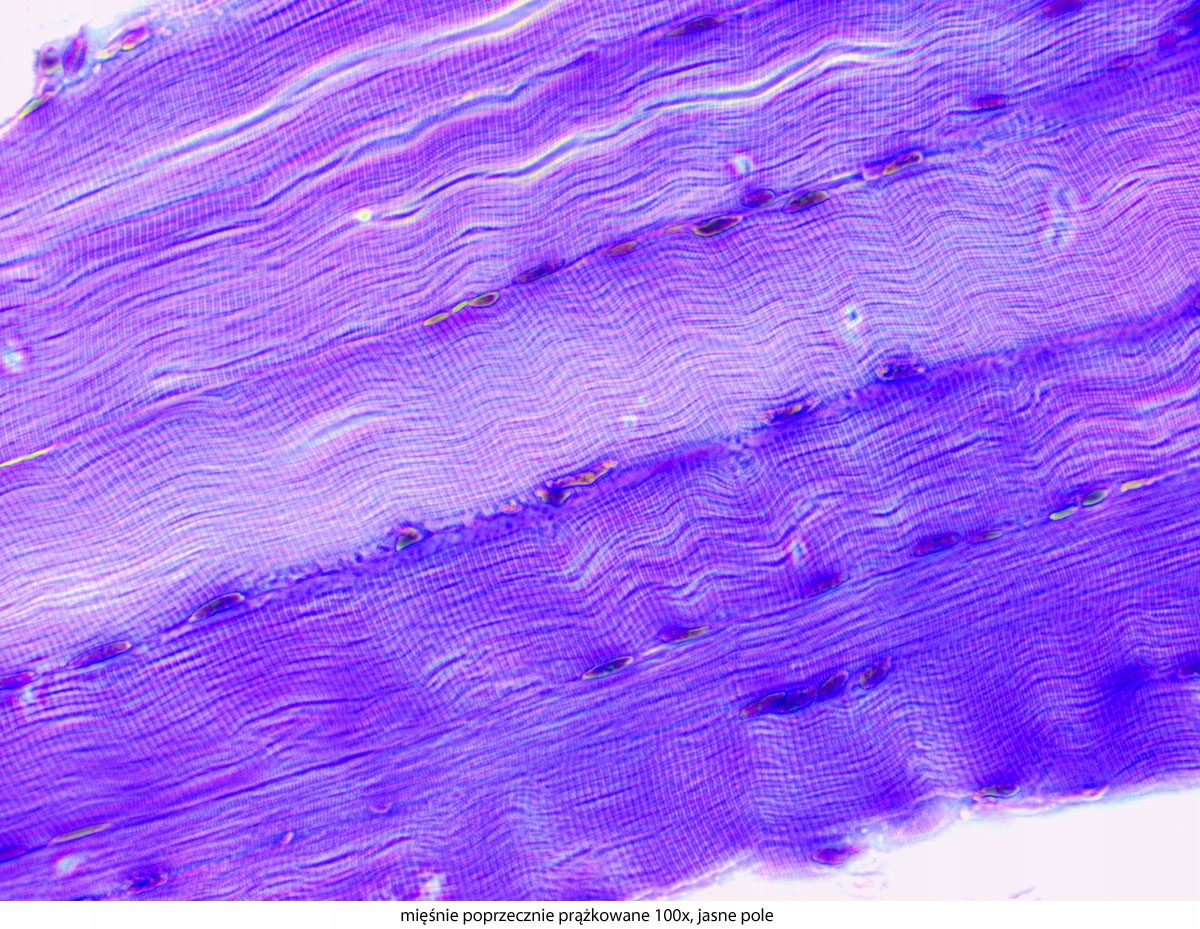

Dlaczego warto wybrać ten konkretny model? Dużą zaletą tego mikroskopu jest stosunek jakości do ceny. Solidna, stabilna i ergonomiczna konstrukcja podstawy gwarantuje wieloletnie użytkowanie. Doskonałe, achromatyczne obiektywy pozwalają na uzyskanie ostrego obrazu i powiększeń w zakresie 40-1000x. Szerokie okulary i jasne oświetlenie LED umożliwiają obserwację nawet bardzo małych obiektów. Stolik mechaniczny i precyzyjnie regulowane śruby do ruchu mikro i makro zapewniają dokładność pracy. Dzięki bogatej ofercie akcesoriów, serię Genetic Pro można rozbudować o inne techniki obserwacji mikroskopowej. Polaryzacja, ciemne pole i kontrast fazowy znacząco poszerzają możliwości tego urządzenia. Szeroki wybór kamer mikroskopowych i adapterów fotograficznych umożliwia dokumentację obrazu w postaci zdjęć i filmów, a zaawansowane oprogramowanie pozwala na późniejszą analizę i obróbkę takiego materiału.

- Technika obserwacji:, Jasne pole

- Możliwość rozbudowy:, ciemne pole, kontrast fazowy, polaryzacja

- Powiększenia mikroskopu:, 40 x100 x400 x1000 x,